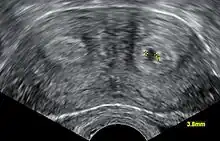

L'échographie utérine est utile à la recherche des causes utérines car celles-ci sont fréquentes et parfois curables. L'échographie, quand elle est orientée, est très performante pour établir un diagnostic différentiel entre utérus cloisonné et bicorne même si l'hystérographie reste la référence dans beaucoup d'autres situations (unicorne, béance, hypoplasie, DES syndrome).